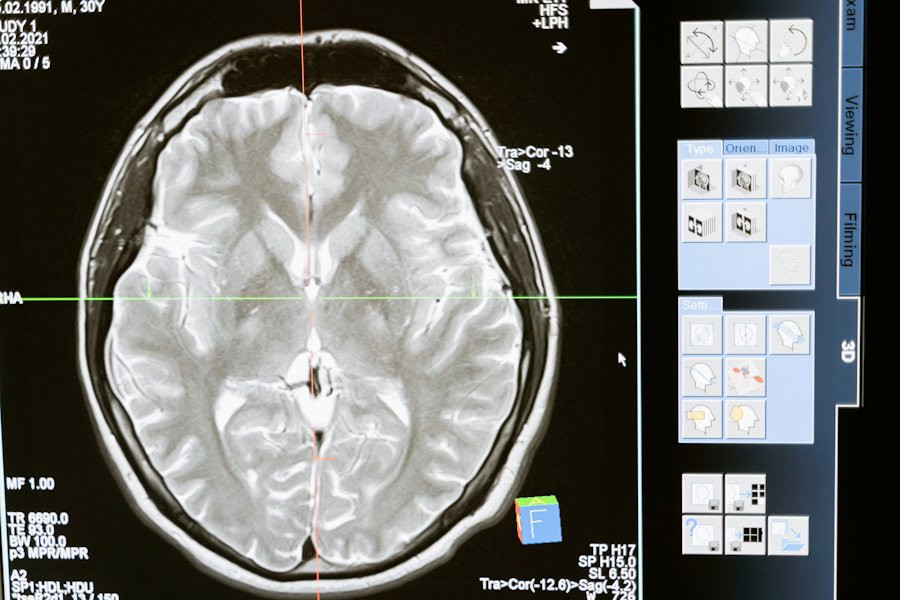

Фото из открытых источников

Их работа сфокусировалась на использовании двух- и трехмерных моделей компьютерного зрения, основанных на анализе данных магнитно-резонансной томографии (МРТ) мозга, как с использованием контрастного вещества, так и без него.